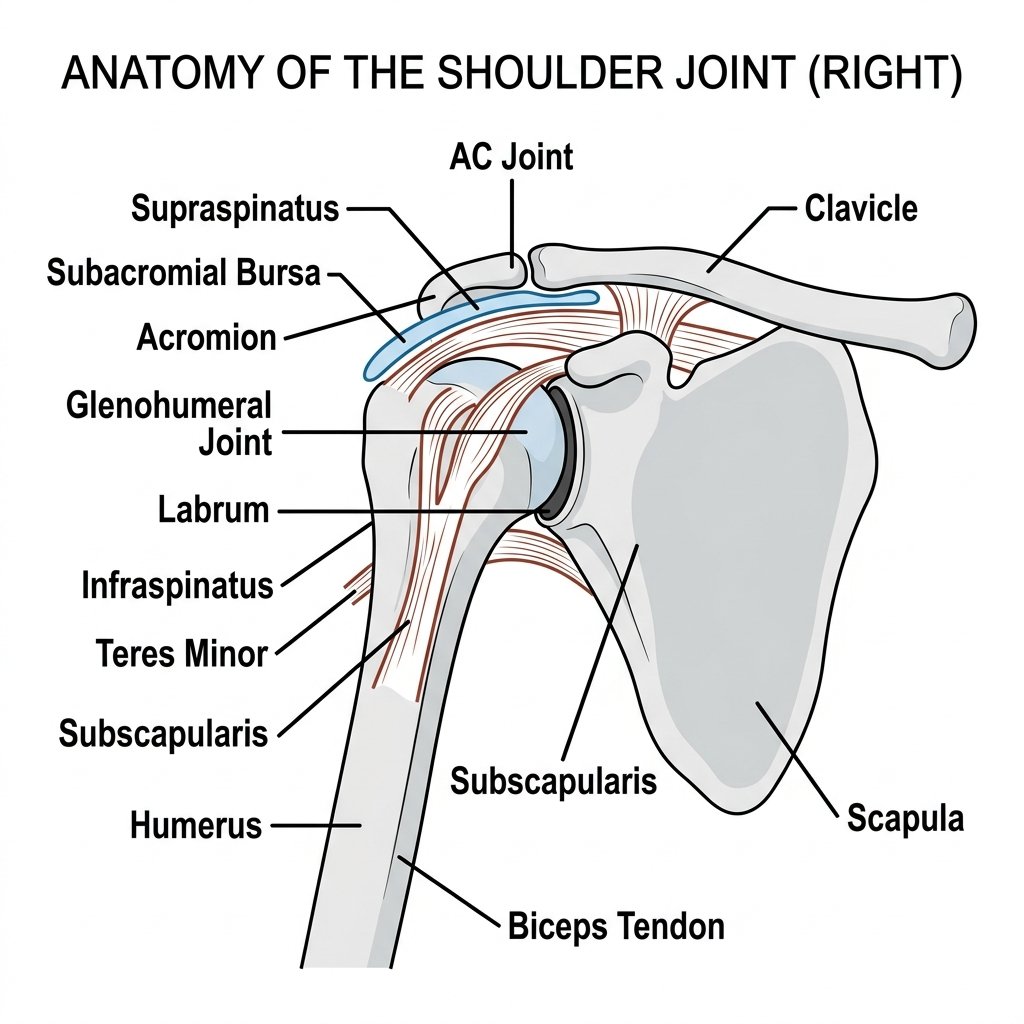

1 Essential Shoulder MRI Scan London Guide

Shoulder MRI scan London provides detailed soft tissue imaging that no other scan can match for depth and comprehensiveness. If...